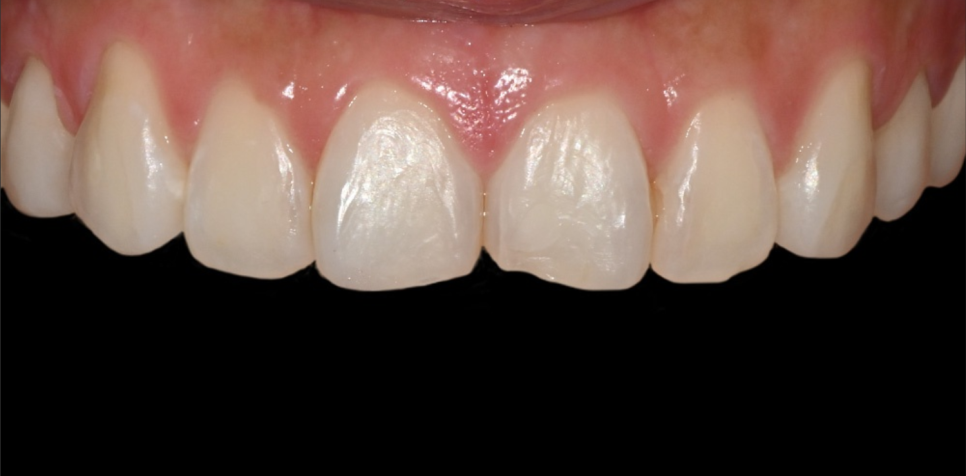

내원 당시 상태

환자분은 기존 보철은 없었지만

앞니 사이 라인이 들쭉하고 밝기가 고르지 않아

사진 찍을 때 늘 앞니가 신경 쓰였다고 하셨어요.

평소 웃을 때 앞니 모양이 조금 흐트러져 보이고,

치아 색이 살짝 탁해 보여

자연스럽게 정리하고 싶다며 내원하셨어요.